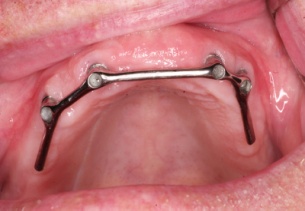

Bezzubá čelist je hlavní indikací pro ošetření pomocí implantátů. Zejména celkové zubní náhrady v dolní čelisti mají velice nízkou stabilitu a držení díky velkému úbytku kosti.

S pomocí zubních implantátů můžeme díky různým kotevním systémům (třmeny, kulové hlavy, Locatory) zajistit stabilitu a držení protézy nebo při použití většího počtu implantátů zhotovit pevné náhrady – můstky nalepené nebo našroubované na pevno na implantáty.

S těmito typy náhrad můžeme dosáhnout perfektní funkci, výbornou estetiku, fonetiku a současně zajistit u pacienta možnost dobré hygienickou péče a čištění, která je pro životnost implantátů velice důležitá.